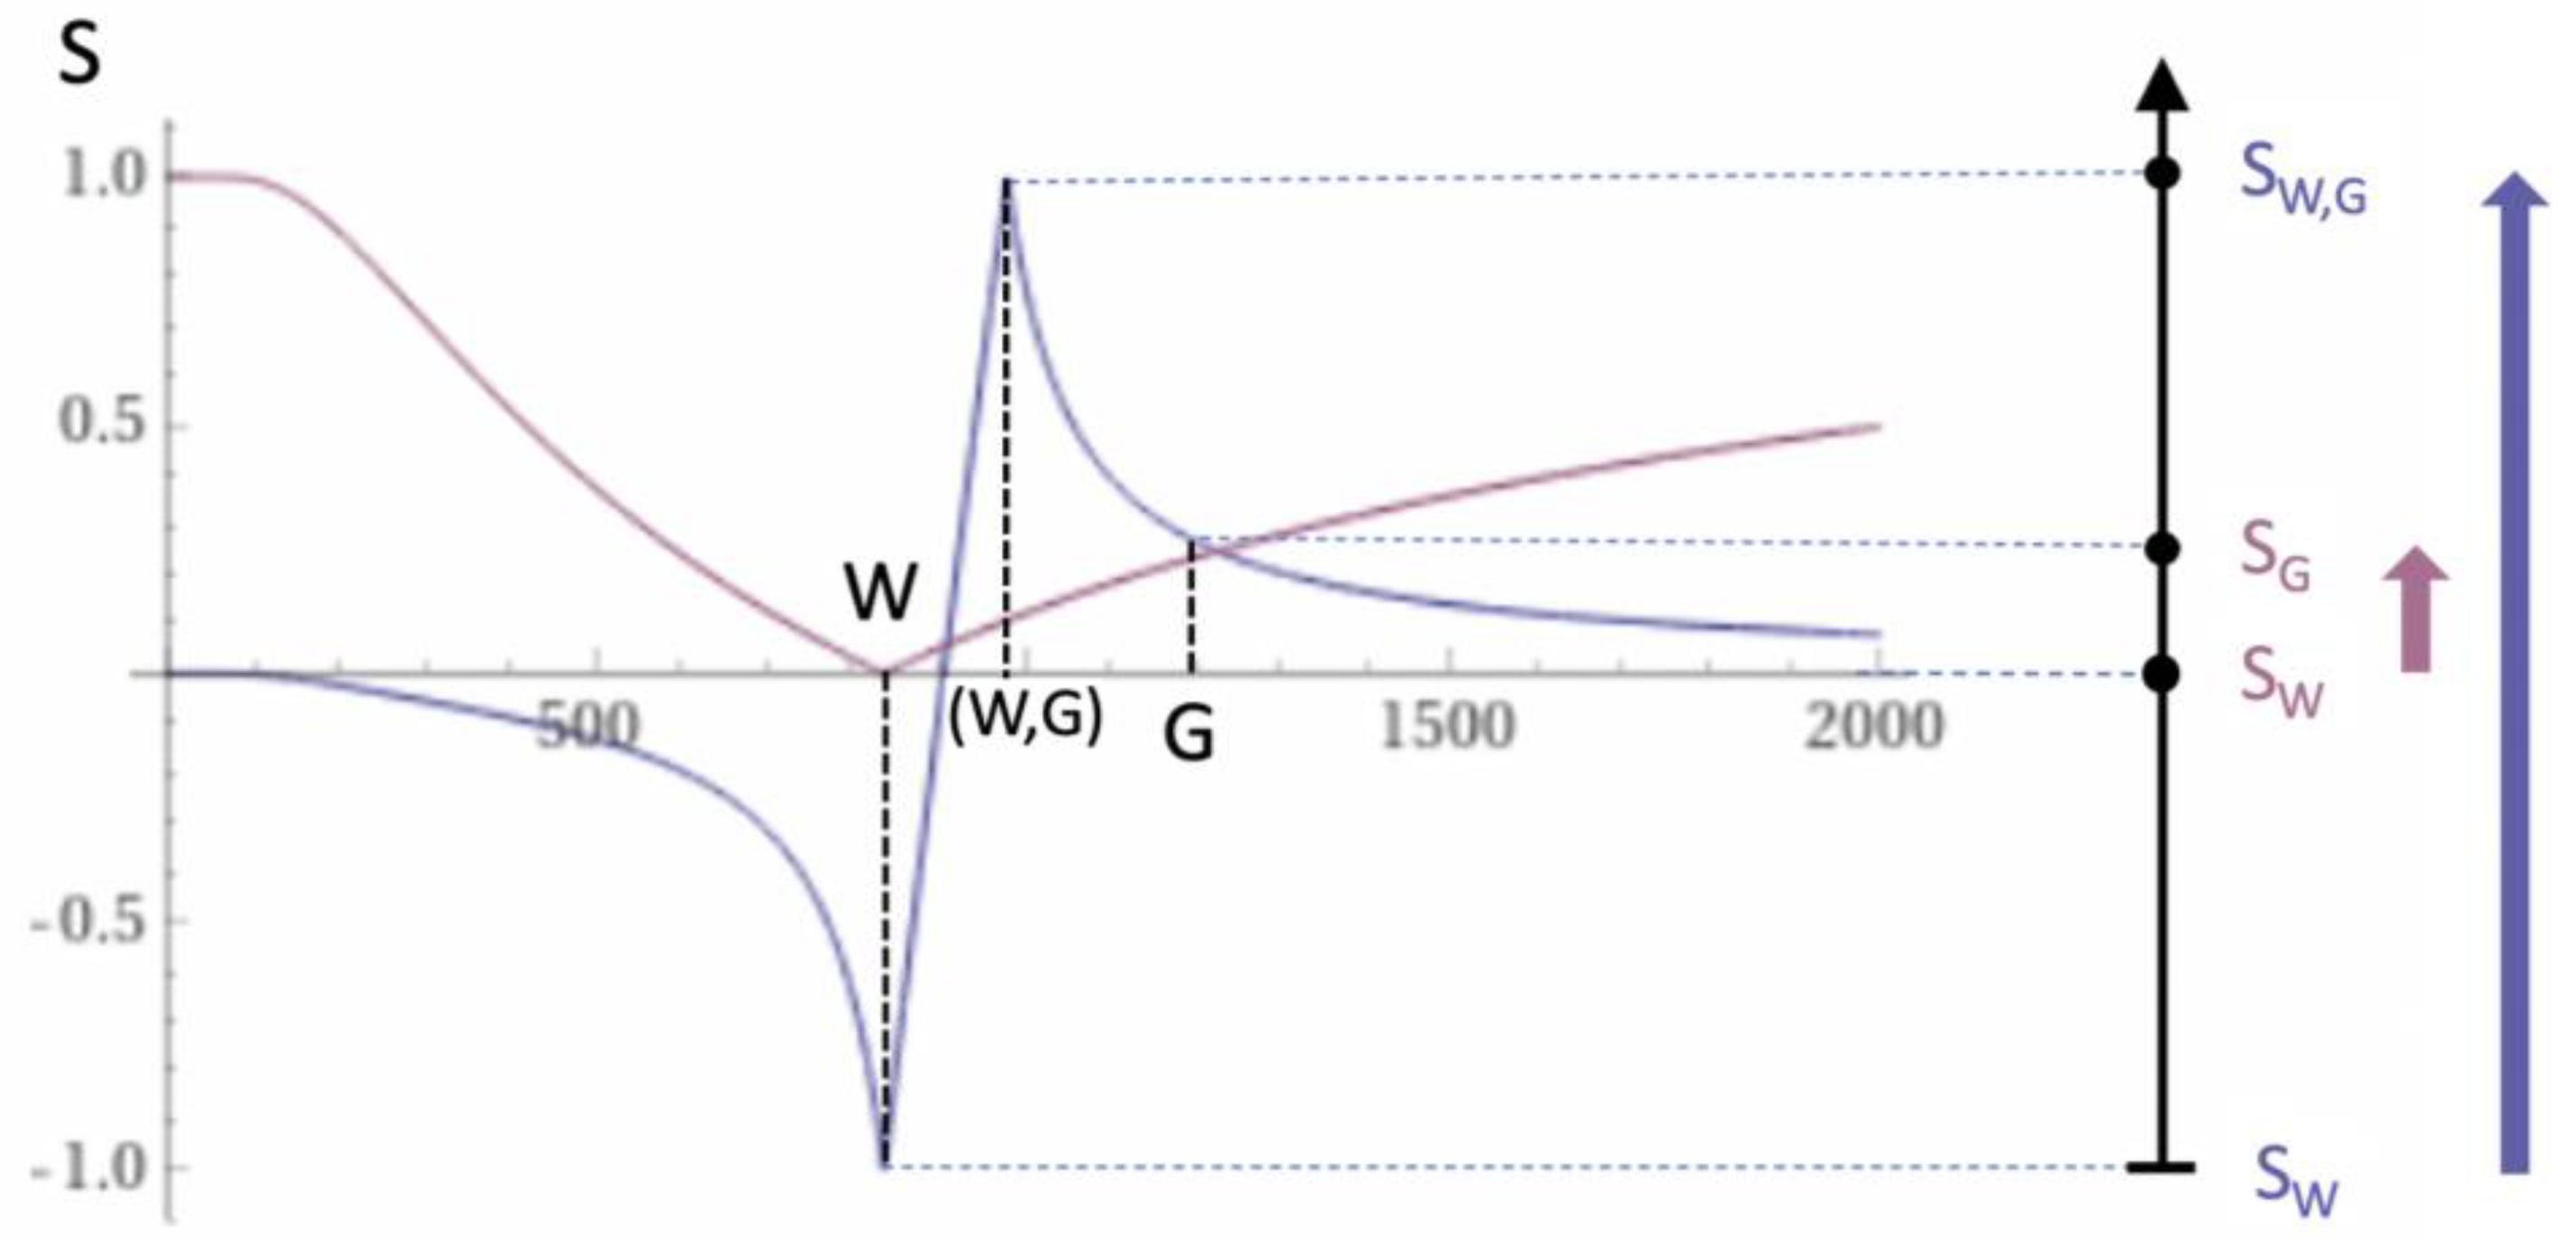

2. Basic Physics

2.1. Tissue Property Filters (TP-Filters) and the Inversion Recovery (IR) Sequence

| 4 | dSIR | Figure 2 and Figure 3 | |

| 7 | dSIR, SdSIR | (in mD) | Figure 2 |

| 8 | dSIR, T1 | (in mD) | Figure 2 |